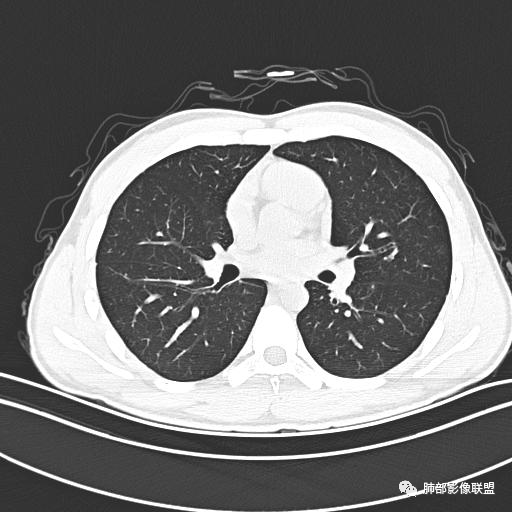

小强:青年,发热,皮疹;双肺散在结节,周围磨玻璃,点晕征,疱疹病毒感染,鉴别荚膜组织胞浆菌,结核。 大雄:青年,急性起病,发热伴全身皮疹2天,抗病毒治疗体温有下降。双肺随机分布大小不等类圆结节,“点晕征”。考虑水痘-疱疹病毒(VZV)血播询问接触史,查体皮疹分布以及形态基本可诊断。 王开金江津中心医院呼吸科:青年男性,起病急,病程短,以发热,皮疹为首发症状,感染指标以单核细胞升高为主,胸部ct双肺多发结界,周围有晕,点晕表现,随机分布,同意於老师意见,水痘疱疹病毒血流感染累及肺。 王秀仙:双肺多发大小不等结节,周围有晕,边缘模糊,呈点晕征表现。青年,急性起病,发热伴全身皮疹2天,抗病毒治疗体温有下降。考虑疱疹病毒。鉴别荚膜组织胞浆菌。 傅昌瑜:19岁男性,发热、全身皮疹2天,单核细胞增高,双肺多发结节,结节边缘见边界不清磨玻璃影。点晕征+发热、全身皮疹+单核细胞增高——考虑水痘-带状疱疹病毒肺炎。 一切∮随缘:年轻男性,发热,皮疹两天,实验室,CRP,PCT增高,影像:双肺多发散在磨玻璃结节,边界欠清,大小不等,呈点晕征改变,以血管束周围分布为主,局部血管束略增粗,其它无明显改变,考虑:1:病毒性肺炎(水痘疱疹病毒?不知道皮肤有无改变)2:真菌(组织胞浆菌,血管侵袭性肺曲霉)3:GPA4:寄生虫(实验室没有看到嗜酸细胞增高) 赵山河:双肺散在结节,周围有晕,边缘模糊,呈点晕征表现。青年,急性起病,发热伴全身皮疹2天,抗病毒治疗体温有下降。考虑水痘—疱疹病毒感染。洪桥爱:青年男性,发热、皮疹2天,伴瘙痒,皮疹于面部首发,之后进展至全身,虽然没有对皮疹进行描述,但是从出疹时间及皮疹进展情况,伴瘙痒,应该就是个水痘患者;CT提示双肺随机分布结节影,部分结节伴有边界不清晕征,考虑水痘血播肺。 刘强:年轻男性,急性起病,皮疹,发热,抗感染治疗体温下降,说明有效。影像表现为散在点晕征,感染类疾病谱(疱疹病毒,真菌,结核),结合年龄,皮肤皮疹,考虑水痘-疱疹病毒性肺炎。 小兜:男性,19岁,发热皮疹两天,颜面部至全身,CRP,降钙素及单核增高。CT示双肺散在小结节,周围伴磨玻璃影,点晕征,考虑为水痘-带状疱疹病毒(varicella-zoster virus,VZV)肺炎 必有路:青年,皮疹+发热+“点晕征”→水痘-疱疹病毒(VZV) 许慧良:青年男性患者,发热、皮疹2天,体温最高38.5℃,第3天皮疹扩展至全身,伴瘙痒,胸部CT:双肺多发随机分布的小结节,结节周边见边界模糊的晕征,考虑水痘病毒感染流心明智:男,19,急性起病,发热伴全身皮疹2天。出疹顺序头→全身,抗病毒有效。胸部CT:两肺多发大小不等类圆形实性小结节影,随机分布,结节周围环绕GGO,边界模糊,呈点晕征。出疹特点是关键,未提示。考虑:血播病毒性肺炎,水痘-疱疹病毒?麻疹?鉴别荚膜组织胞浆菌、TB、血管炎、寄生虫等。 浪迹天涯:病灶多为5-10mm大小结节,结节周围可见磨玻璃样的晕环,常多发,可分布于肺内任何区域,考虑水痘—带状疱疹病肺炎如果短时间内有新的一个区域浸润,更加能说明,